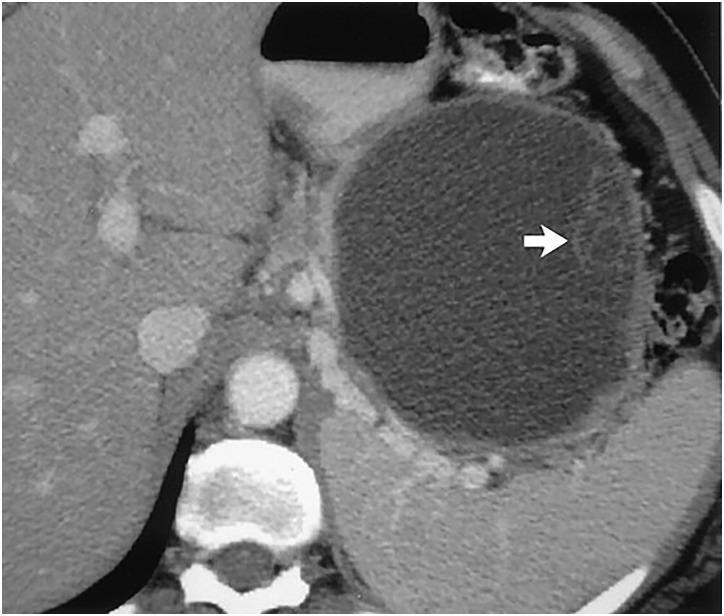

Pancreatic cystic lesions can be benign, premalignant or malignant. The recent increase in detection and tremendous clinical variability of pancreatic cysts has presented a significant therapeutic challenge to physicians. Mucinous cystic neoplasms are of particular interest given their known malignant potential. This review article provides a brief but comprehensive review of premalignant pancreatic cystic lesions with advanced endoscopic ultrasound (EUS) management approaches. A comprehensive literature search was performed using PubMed, Cochrane, OVID and EMBASE databases. Preneoplastic pancreatic cystic lesions include mucinous cystadenoma and intraductal papillary mucinous neoplasm. The 2012 International Sendai Guidelines guide physicians in their management of pancreatic cystic lesions. Some of the advanced EUS management techniques include ethanol ablation, chemotherapeutic (paclitaxel) ablation, radiofrequency ablation and cryotherapy. In future, EUS-guided injections of drug-eluting beads and neodymium:yttrium aluminum agent laser ablation is predicted to be an integral part of EUS-guided management techniques. In summary, International Sendai Consensus Guidelines should be used to make a decision regarding management of pancreatic cystic lesions. Advanced EUS techniques are proving extremely beneficial in management, especially in those patients who are at high surgical risk.